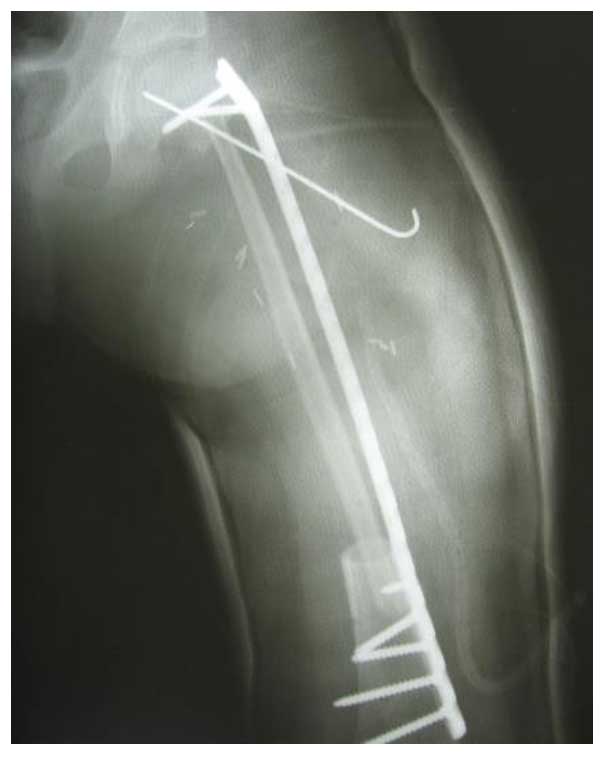

Ameliyat Sonrası: Röntgende çıkarılan tümörlü kemiğin yerine uygulanan vaskülerize fibulanın plak ve K teli ile fiksasyonu görülmekte.